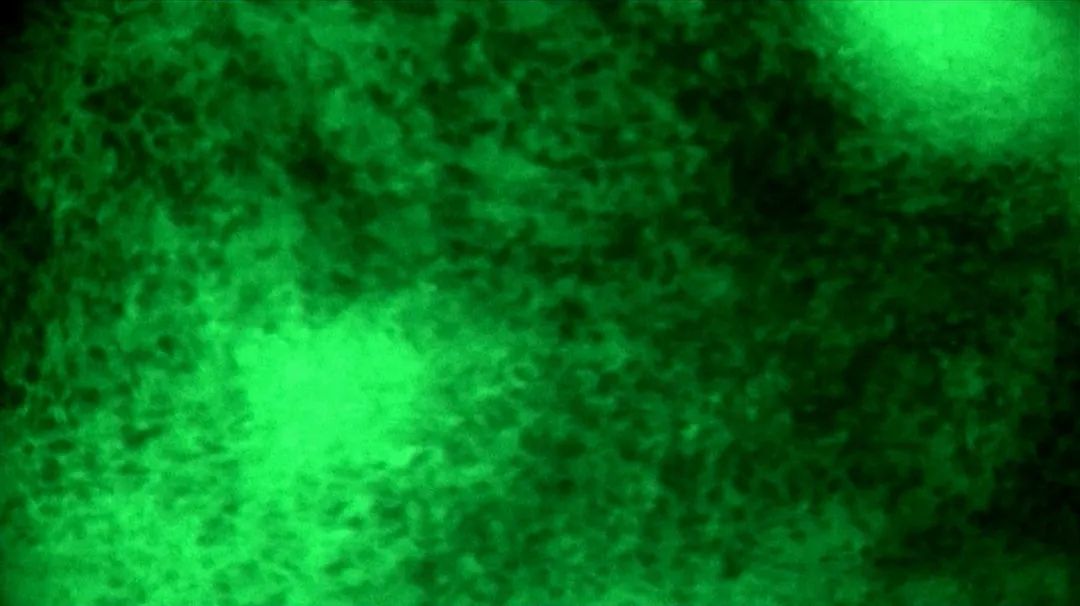

醫(yī)生在術(shù)中導(dǎo)航及電生理監(jiān)測(cè)下將腫瘤病灶主體切除后,使用EndoSCell?對(duì)瘤腔進(jìn)行了近10分鐘滑動(dòng)式掃描檢查,在瘤腔側(cè)緣發(fā)現(xiàn)了一處細(xì)胞核呈明顯異型、分布密集且不規(guī)則的組織,判斷為殘留病灶并進(jìn)行擴(kuò)切。隨后再次使用EndoSCell?探查,圖像顯示整個(gè)瘤腔均為正常細(xì)胞形態(tài),由此判定切緣陰性,可進(jìn)入關(guān)顱等后續(xù)步驟。

醫(yī)生在術(shù)中使用EndoSCell?掃查瘤腔

腫瘤細(xì)胞與正常細(xì)胞的ES圖像對(duì)比

陽(yáng)性:細(xì)胞核異型、密集、分布不均勻

陰性:細(xì)胞核形態(tài)正常、分布均勻